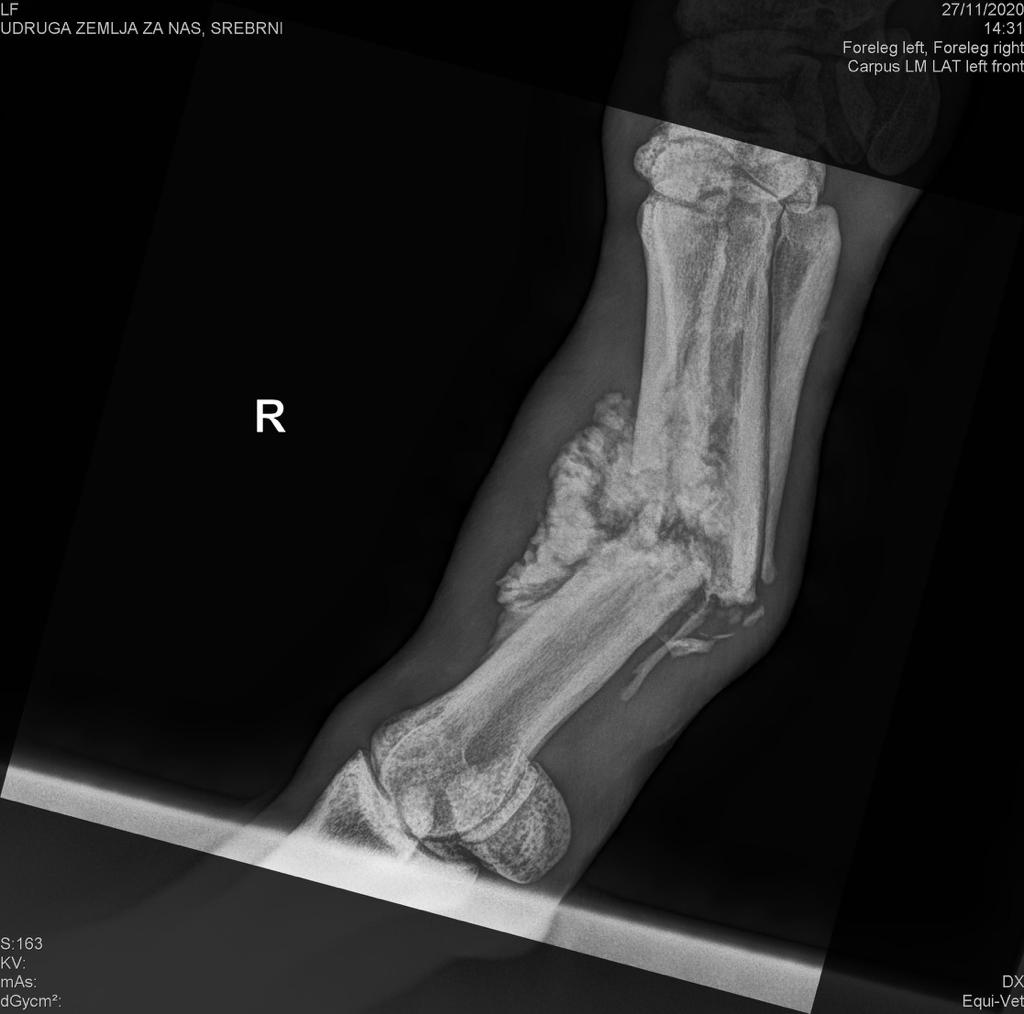

Srebrni je sedmogodišnji konj u tipu dalmatinskog tovarnog ili bosanskog brdskog konja koji je većinu svog života proveo kao radni konj imenom Berac, noseći terete po nepristupačnom bračkom terenu. Prije dva mjeseca slomio je nogu i brigu o njemu preuzele su članice

ekološke udruge Zemlja za nas, koje ovim putem upućuju poziv javnosti za prikupljanje sredstava za nužnu operaciju, koja će Srebrnom omogućiti da preživi.

Operaciju nažalost nije moguće izvesti u Hrvatskoj, već Srebrni mora na put u Beč. Cijena operacije, postoperativnog tretmana koji će trajati do osam tjedana i najma vozila za transport Srebrnog je 10.000 eura. Procjena je to dr. vet. Karstena Veldea s bečkog Veterinarskog sveučilišta, koja se temelji na RTG snimci koju je napravio zagrebački dr. vet. Goran Csik, koji je Srebrnog snimio na pokretnom rentgenu, za ovu priliku posebno dopremljenom iz Zagreba na Brač.